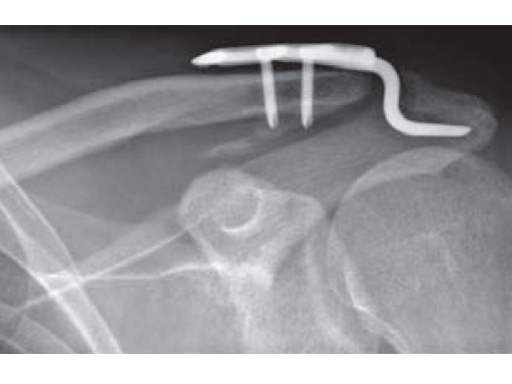

Fig.

Follow-up x-ray after 10 weeks. Begining ossification in coracoclavicular ligament.